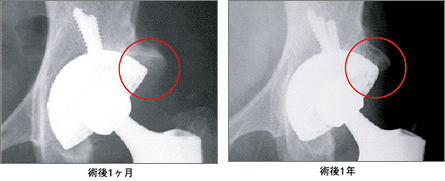

AHFIX技術を活用した人工股関節の臨床的有用性を検証するために、2年半にわたる臨床試験が実施されました。

その結果、日本整形外科学会股関節機能判定基準では、疼痛、歩行能力、可動域及び日常動作の全ての項目において改善が認められました。

また、X線学的評価では、人工股関節と骨とのギャップが消失した(特に臼蓋側)症例が70関節中22関節に認められ、良好なBone Conductionの発現を裏付けているように思われた、と報告されています。